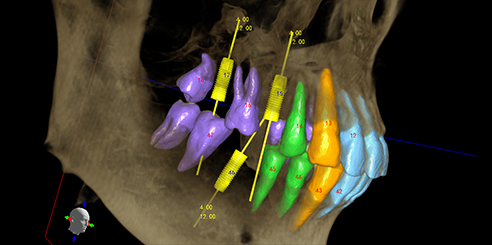

Model Scan (Optional) – Dental CBCT Support

In addition, optional model scanning allows accurate digital impressions and prosthetic planning, making this system ideal for both orthodontic and implant applications.

Next, Nerve Detection with Dental CBCT (AI+Nerve)

The system automatically identifies and labels the neural tube within the CT image.

This function simplifies diagnosis and supports more precise surgical planning.

T-MAR Metal Artifact Reduction in LargeV Dental CBCT

With the new T-MAR module, the system automatically removes metal artifacts and corrects image distortions intelligently.

Hence, the final images remain clear, accurate, and clinically reliable.